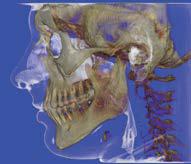

L’innovazione e la sicurezza sono due dei valori perseguiti dallo Studio Braconi a Terni, un punto di riferimento nell’ambito della radiologia 3D ortopedica grazie alla presenza del macchinario Newton 5G XL: si tratta dell’unico apparecchio nel Centro Italia che permette di eseguire una perfetta diagnostica per immagini in ortopedia e per la cervicale, oltre per le piccole articolazioni come seni paranasali, orecchie, colonna cervicale, gomito, polso, mano, ginocchio, caviglia e piede.

Nell’ambito della radiologia 3D ortopedica, il centro diagnostico utilizza il nuovissimo macchinario NewTom 5G XL, in grado di individuare con la massima precisione la presenza di fratture o lussazioni delle articolazioni, controllare la corretta guarigione di una frattura, valutare una lesione o una ferita causata da infezione, artrite o crescita anormale dell’osso.

Il tutto mediante una semplice e veloce scansione, grazie alla quale si otterranno diverse immagini in 3D ad altissima risoluzione e, per ottenere immagini ancora più nitide mediante un bassissimo dosaggio di radiazioni, gli esperti si avvalgono dell’innovazione racchiusa nella tecnologia Cone Beam.

Se con la radiologia tradizionale era necessario eseguire scansioni multiple, la novità introdotta dal macchinario NewTom 5G XL risiede nella capacità di fornire immagini ad alta risoluzione in un’unica scansione, mostrando nitidamente i dettagli delle articolazioni degli arti superiori e inferiori. Inoltre, a differenza della tecnologia 2D, la radiologia 3D ortopedica permette di individuare immediatamente alcune patologie come quella del metatarso, la quale richiede un allineamento visivo dedicato o una diagnosi delle micro fratture ossee.

Un altro valore aggiunto che rende la radiologia 3D ortopedica uno strumento fondamentale nell’ambito della diagnostica per immagini attuale è la bassissima dose di radiazioni emesse: infatti, la tecnologia CBCT garantisce una dose fino a 10 volte inferiore rispetto al MSCT.